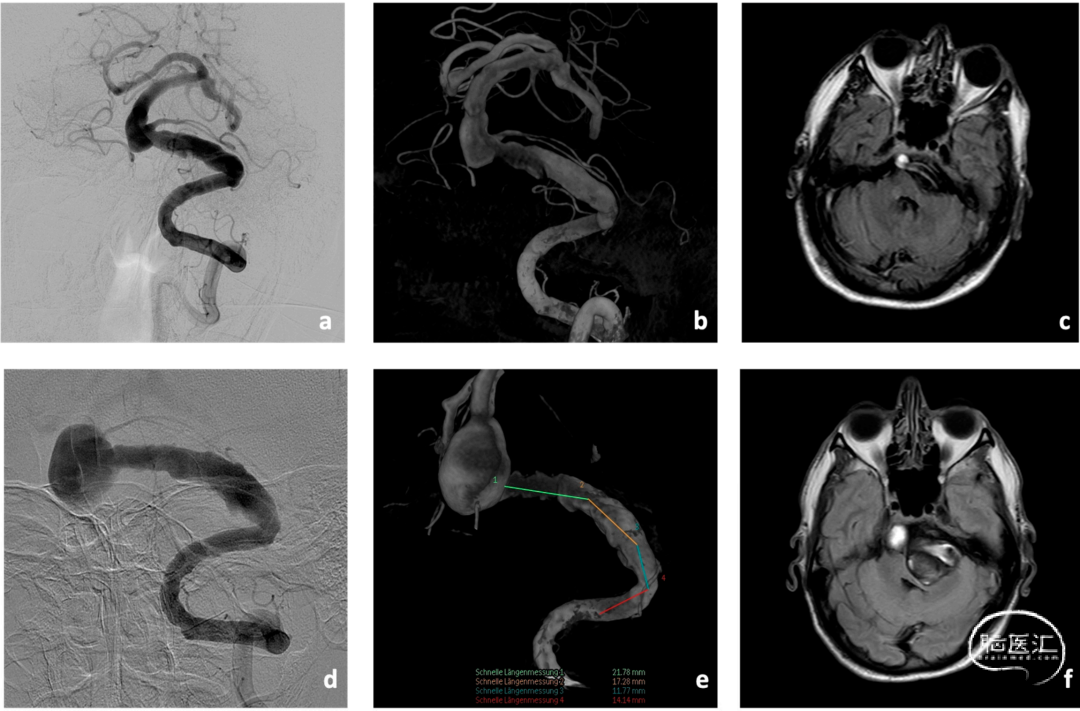

患者1以复视、行走不稳、共济失调于2018年就诊,该患者既往高血压病史、长期吸烟史(40包/年),经影像检查确诊为BA动脉瘤(大小约10×11mm),伴左侧椎动脉V4段梭形扩张(长度约35mm,图2示),伴有右侧椎动脉发育不全。经神经外科、神经内科、介入神经放射科MDT后建议保守,强化降压治疗。

图2. 患者1在2018年时影像检查(a-c),2022年影像检查资料(d-f)。动脉瘤较前明显增大且动脉瘤腔内血栓导致明显的占位效应。

四年后患者神经功能明显恶化,现存在严重构音障碍、吞咽困难、左侧偏瘫、左侧面瘫、永久性步态障碍。CTA显示动脉瘤较前明显增大,最大直径为15×22mm。且已明显压迫脑干(8×30mm)。经过对DSA重建结果的研究,提出了分期治疗概念,即在一期干预中使用Accero®-Rex支架进行联合治疗,然后在二期干预中对动脉瘤残余进行血流导向治疗(图3)。